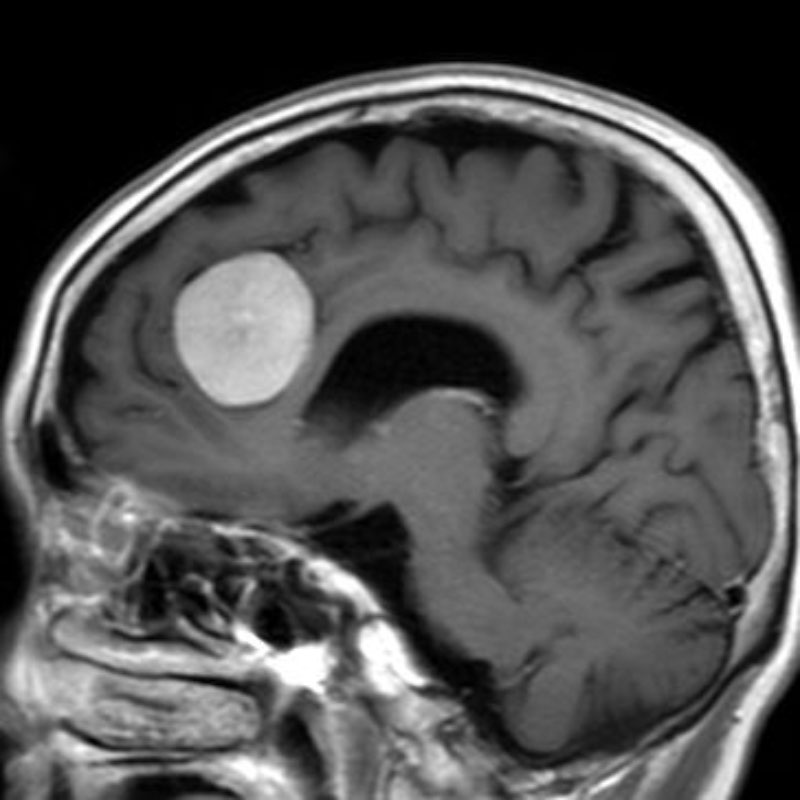

503

'24年1月

30代

大脳鎌右側髄膜腫

頭蓋内腫瘍摘出術

No.’24_5 手術前1

No.’24_5 手術前2